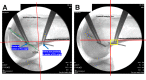

Methods: Using a pilot cadaveric specimen, the center of the radiographic safe isometric area for femoral fixation of LET, defined as a 1 cm (proximal-distal) area located proximal to the metaphyseal flare and posterior to the posterior cortical extension line (PCEL), was located using fluoroscopy and found to be 20 mm directly proximal to the center of the fibular collateral ligament (FCL) origin. Using 10 additional specimens, the center of the FCL origin and a location 20 mm directly proximal was identified. K-wires were placed at each location. A lateral radiograph was obtained, and distances of the proximal K-wire relative to the PCEL and metaphyseal flare were measured. The location of the proximal K-wire relative to the radiographic safe isometric area was assessed by 2 independent observers. Intrarater and inter-rater reliability was calculated for all measurements using intraclass coefficients (ICCs).

Results: There was excellent intrarater and inter-rater reliability for all radiographic measurements (.908 to .975 and .968 to .988, respectively). In 5/10 specimens, the proximal K-wire was outside of the radiographic safe isometric area, with 4/5 anterior to the PCEL. Overall, the mean distance from the PCEL was 1 mm ± 4 mm (anterior), and the mean distance from the metaphyseal flare was 7.4 mm ± 2.9 mm (proximal).